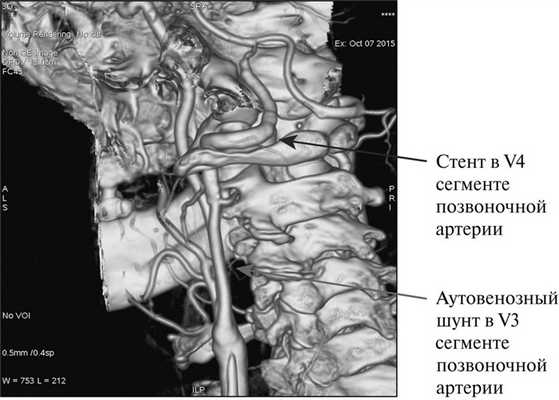

При контрольном осмотре неврологом отмечено улучшение статики и координации, походка стала устойчивой, уменьшение головокружений, исчезновение шума. Данное улучшение сохраняется в течение 6 мес. При дуплексном сканировании магистральных артерий головы: общая СА, внутренняя СА и наружная СА проходимы, кровоток в них магистрального типа, без признаков рестеноза, шунт проходим, диаметр шунта 4,8 мм, линейная скорость кровотока (ЛСК) 0,62 м/с, объемная скорость кровотока 122 мл/мин. Выполнена КТ-ангиография (рис. 6).

Рис. 6. Пациент С. КТ-ангиография через 6 мес после операции.